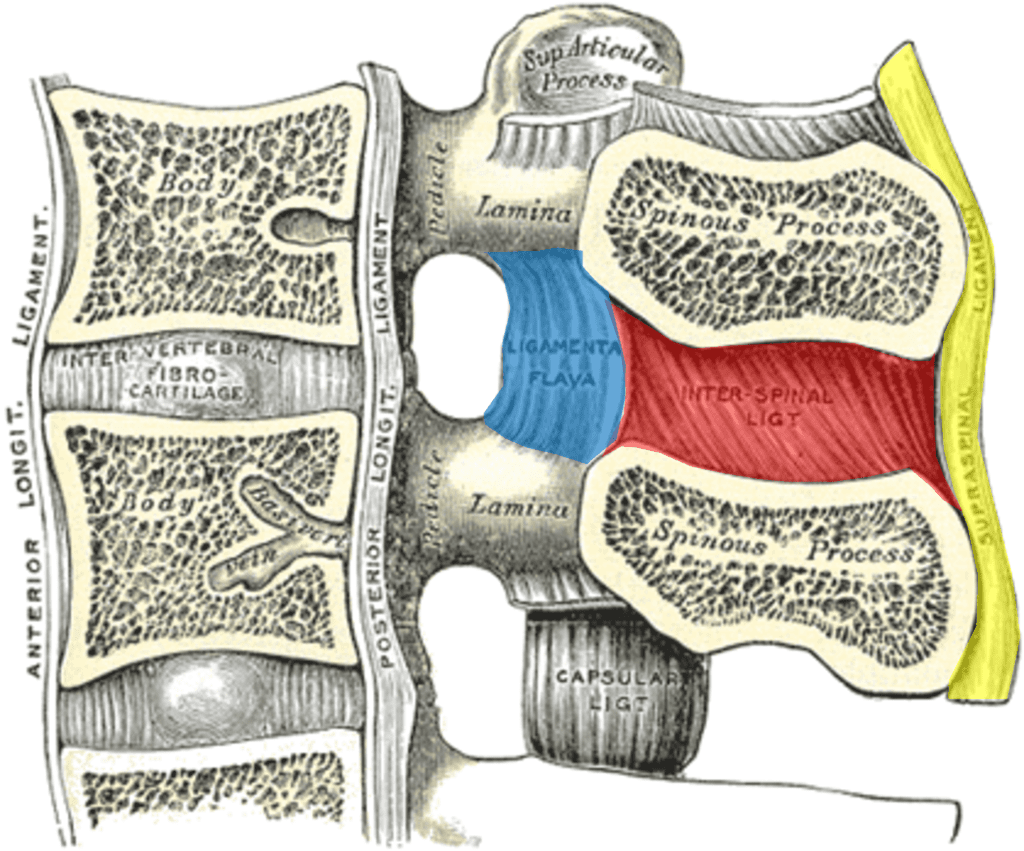

Notes on Anatomy and Physiology: The Spinal Ligaments – Holding All The Parts Together |

The vertebral column usually contains three curves. The cervical and lumbar curves are convex anteriorly, and the thoracic curve is convex posteriorly. These curves, together with gravity, barricity of the local anesthetic,